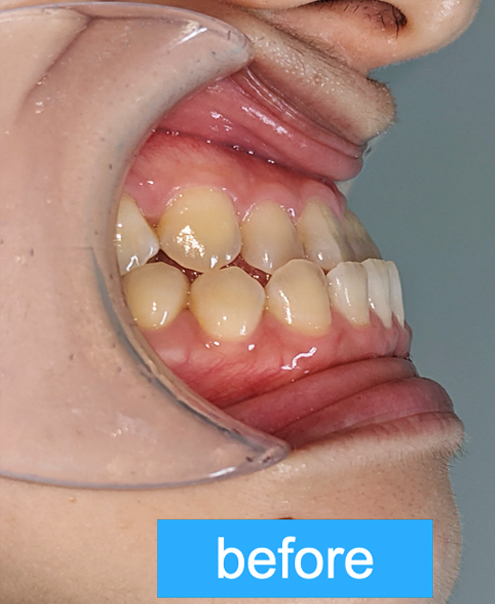

- 主訴

- 前歯が気になる(上下)

- 診断名あるいは主な症状

- 叢生

- 年齢

- 22才

- 治療に用いた主な装置

- マウスピース

- 抜歯部位/抜歯有無

- 無し

- 治療期間

- 約半年

- 総費用

- ¥840,000

- 主なリスク・副作用

- 歯肉退縮,歯根吸収,疼痛,咬合の違和感,装置の違和感,虫歯,歯肉炎